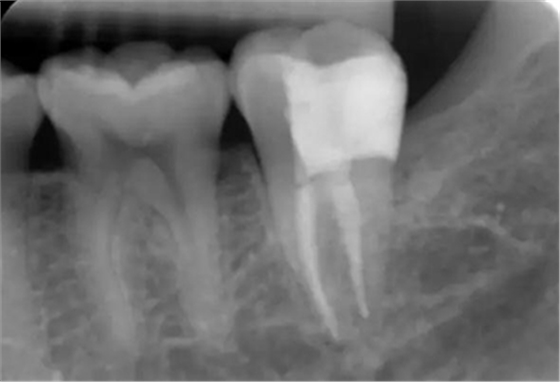

圖2 術(shù)前X片示遠(yuǎn)中鄰面牙體低密度影累及髓角

臨床檢查:37遠(yuǎn)中鄰面探及深齲洞,探痛明顯,叩-,無松動(dòng),冷刺激痛明顯,去除刺激后疼痛延遲。X片示37遠(yuǎn)中鄰面牙體低密度影累及髓角。